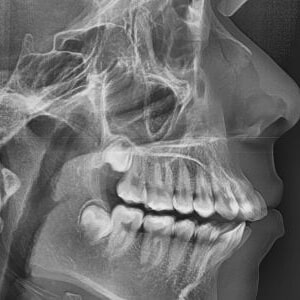

Before any treatment may begin, a consultation will be required to perform a complete examination with X-rays. During the pre-treatment consultation, feel free to ask any questions you have about your treatment. When you are fully informed about your care, you and our team will decide together to proceed with the treatment.